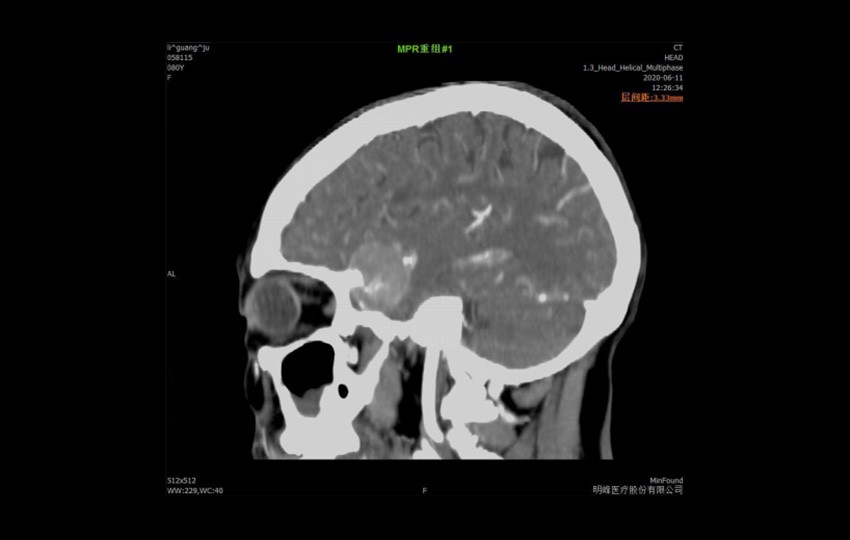

Caso 1-1<br>Meningioma

Caso 1-1

Meningioma